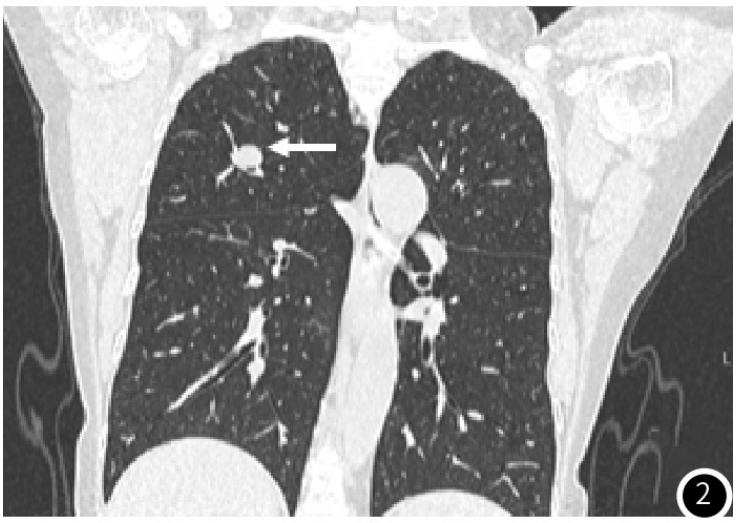

示胰头类圆形低密度结节,大小约14mm×12mm,增强扫描动脉期结节明显均匀强化(图1),强化程度高于正常胰腺实质,静脉期强化减低,边界清;术后4年常规胸腹部CT

图2 冠状位肺窗重建右肺上叶结节,边缘光滑(白箭头);